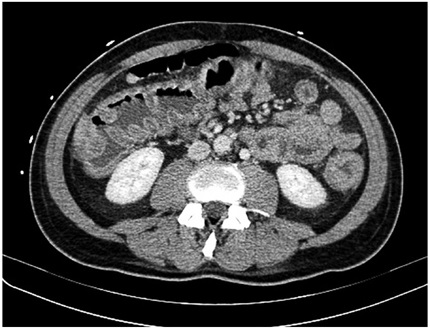

Inicialmente, se consideró choque mixto hipovolémico y séptico de origen gastrointestinal, se inició cubrimiento antibiótico con ampicilina-sulbactam y metronidazol intravenosos y manejo en unidad de cuidado intensivo (UCI). La tomografía computarizada de abdomen informó engrosamiento de las paredes del marco cólico y del recto, con realce anormal de la mucosa, hallazgos compatibles con pancolitis (figura 1).